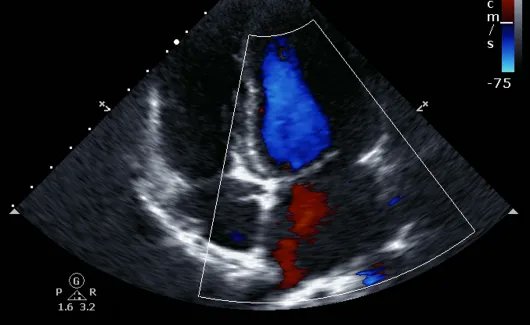

El desarrollo de herramientas tecnológicas para la obtención de imágenes y datos fisiológicos del corazón ha experimentado avances significativos gracias a la evolución de técnicas de diagnóstico por imagen. El ecocardiograma, en particular, ha jugado un papel crucial en la visualización del corazón y en la evaluación de su funcionamiento, permitiendo obtener imágenes detalladas de sus estructuras y movimientos. Este tipo de diagnóstico no invasivo ha tenido un impacto fundamental en la medicina cardiovascular, dado que proporciona una forma eficaz y segura para estudiar el corazón en tiempo real.

La llegada del ecocardiograma bidimensional marcó un hito significativo en la evolución de la imagenología cardíaca, ya que permitió obtener representaciones visuales más detalladas y precisas de las estructuras del corazón en tiempo real. Este avance no solo transformó la forma en que se capturaban las imágenes, sino que también planteó nuevos desafíos en cuanto a su registro y almacenamiento. Para satisfacer esta necesidad, los investigadores y profesionales médicos comenzaron a explorar diferentes métodos que permitieran la grabación de las imágenes bidimensionales de manera eficaz y accesible.

Una de las principales ventajas de la grabación digital fue la posibilidad de realizar comparaciones lado a lado de las imágenes de diferentes momentos en el tiempo. Esto facilitó el análisis de la evolución de las patologías cardíacas, permitiendo a los médicos comparar de forma inmediata los cambios en el corazón del paciente entre estudios previos y actuales. Además, la digitalización facilitó la implementación de herramientas para realizar mediciones precisas sobre las imágenes. Con el software adecuado, los ecocardiogramas digitalizados permitían calcular con mayor exactitud las dimensiones cardíacas, la fracción de eyección y otros parámetros clave, lo que mejoró la precisión diagnóstica.

Inicialmente, las imágenes digitales se obtenían a través de un proceso de digitalización de las señales de vídeo analógicas o de las cintas de vídeo previamente grabadas. Este proceso permitía convertir las imágenes en un formato digital que pudiera almacenarse y manipularse con las ventajas inherentes a la digitalización. No obstante, en los últimos años, la tecnología avanzó hasta permitir la salida digital directa desde los propios equipos ecográficos, sin necesidad de realizar una digitalización intermedia. Esto facilitó aún más el flujo de trabajo y mejoró la calidad de las imágenes, ya que el proceso de conversión de señal analógica a digital, que podría introducir distorsiones, fue eliminado.

La estandarización de las imágenes digitales en la práctica clínica fue posible gracias a la adopción de formatos como el DICOM (Digital Imaging and Communication in Medicine). El algoritmo DICOM se convirtió en un estándar internacional para la comunicación y almacenamiento de imágenes médicas, no solo en ecocardiografía, sino en una amplia gama de modalidades de imagen médica. Su implementación permitió una integración más eficiente de las imágenes ecocardiográficas en los sistemas de información hospitalaria (HIS) y en los sistemas de archivo y comunicación de imágenes médicas (PACS), lo que mejoró la accesibilidad y el intercambio de información entre diferentes dispositivos y centros médicos. Además, DICOM permitió la inclusión de información adicional relevante en las imágenes, como datos del paciente, detalles técnicos del estudio y otras métricas clínicas, lo que favoreció una mejor gestión y organización de la información médica.